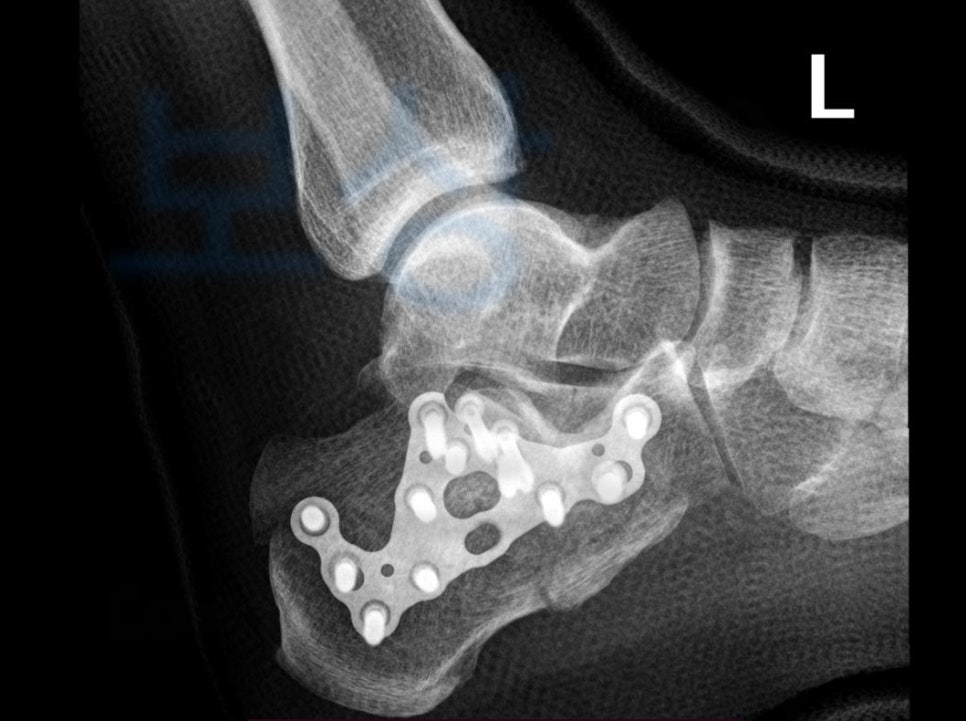

전@@님의 사례입니다. 당시 의뢰인은 아이와 함께 초등학교 담벼락에서 뛰어내리다 발뒤꿈치가 골절되는 재해를 당하셨습니다.

위 응급 기록을 보시면 사고 경위가 자세히 나와 있습니다. 이 사고로 고객님은

종골의 골절, 폐쇄성 s92.00

진단을 받았고 금속 고정술을 시행하셨습니다. 내 보험의 후유장해 항목에서 보상받을 수 있습니다. 의뢰인의 보험 증권을 보면

족관절의 기능에 약간의 장해 5% 영구 장해 인정받았습니다. 저희는 위 진단서를 기초로 손해사정서 및 증빙자료를 각 보험사에 청구하였고